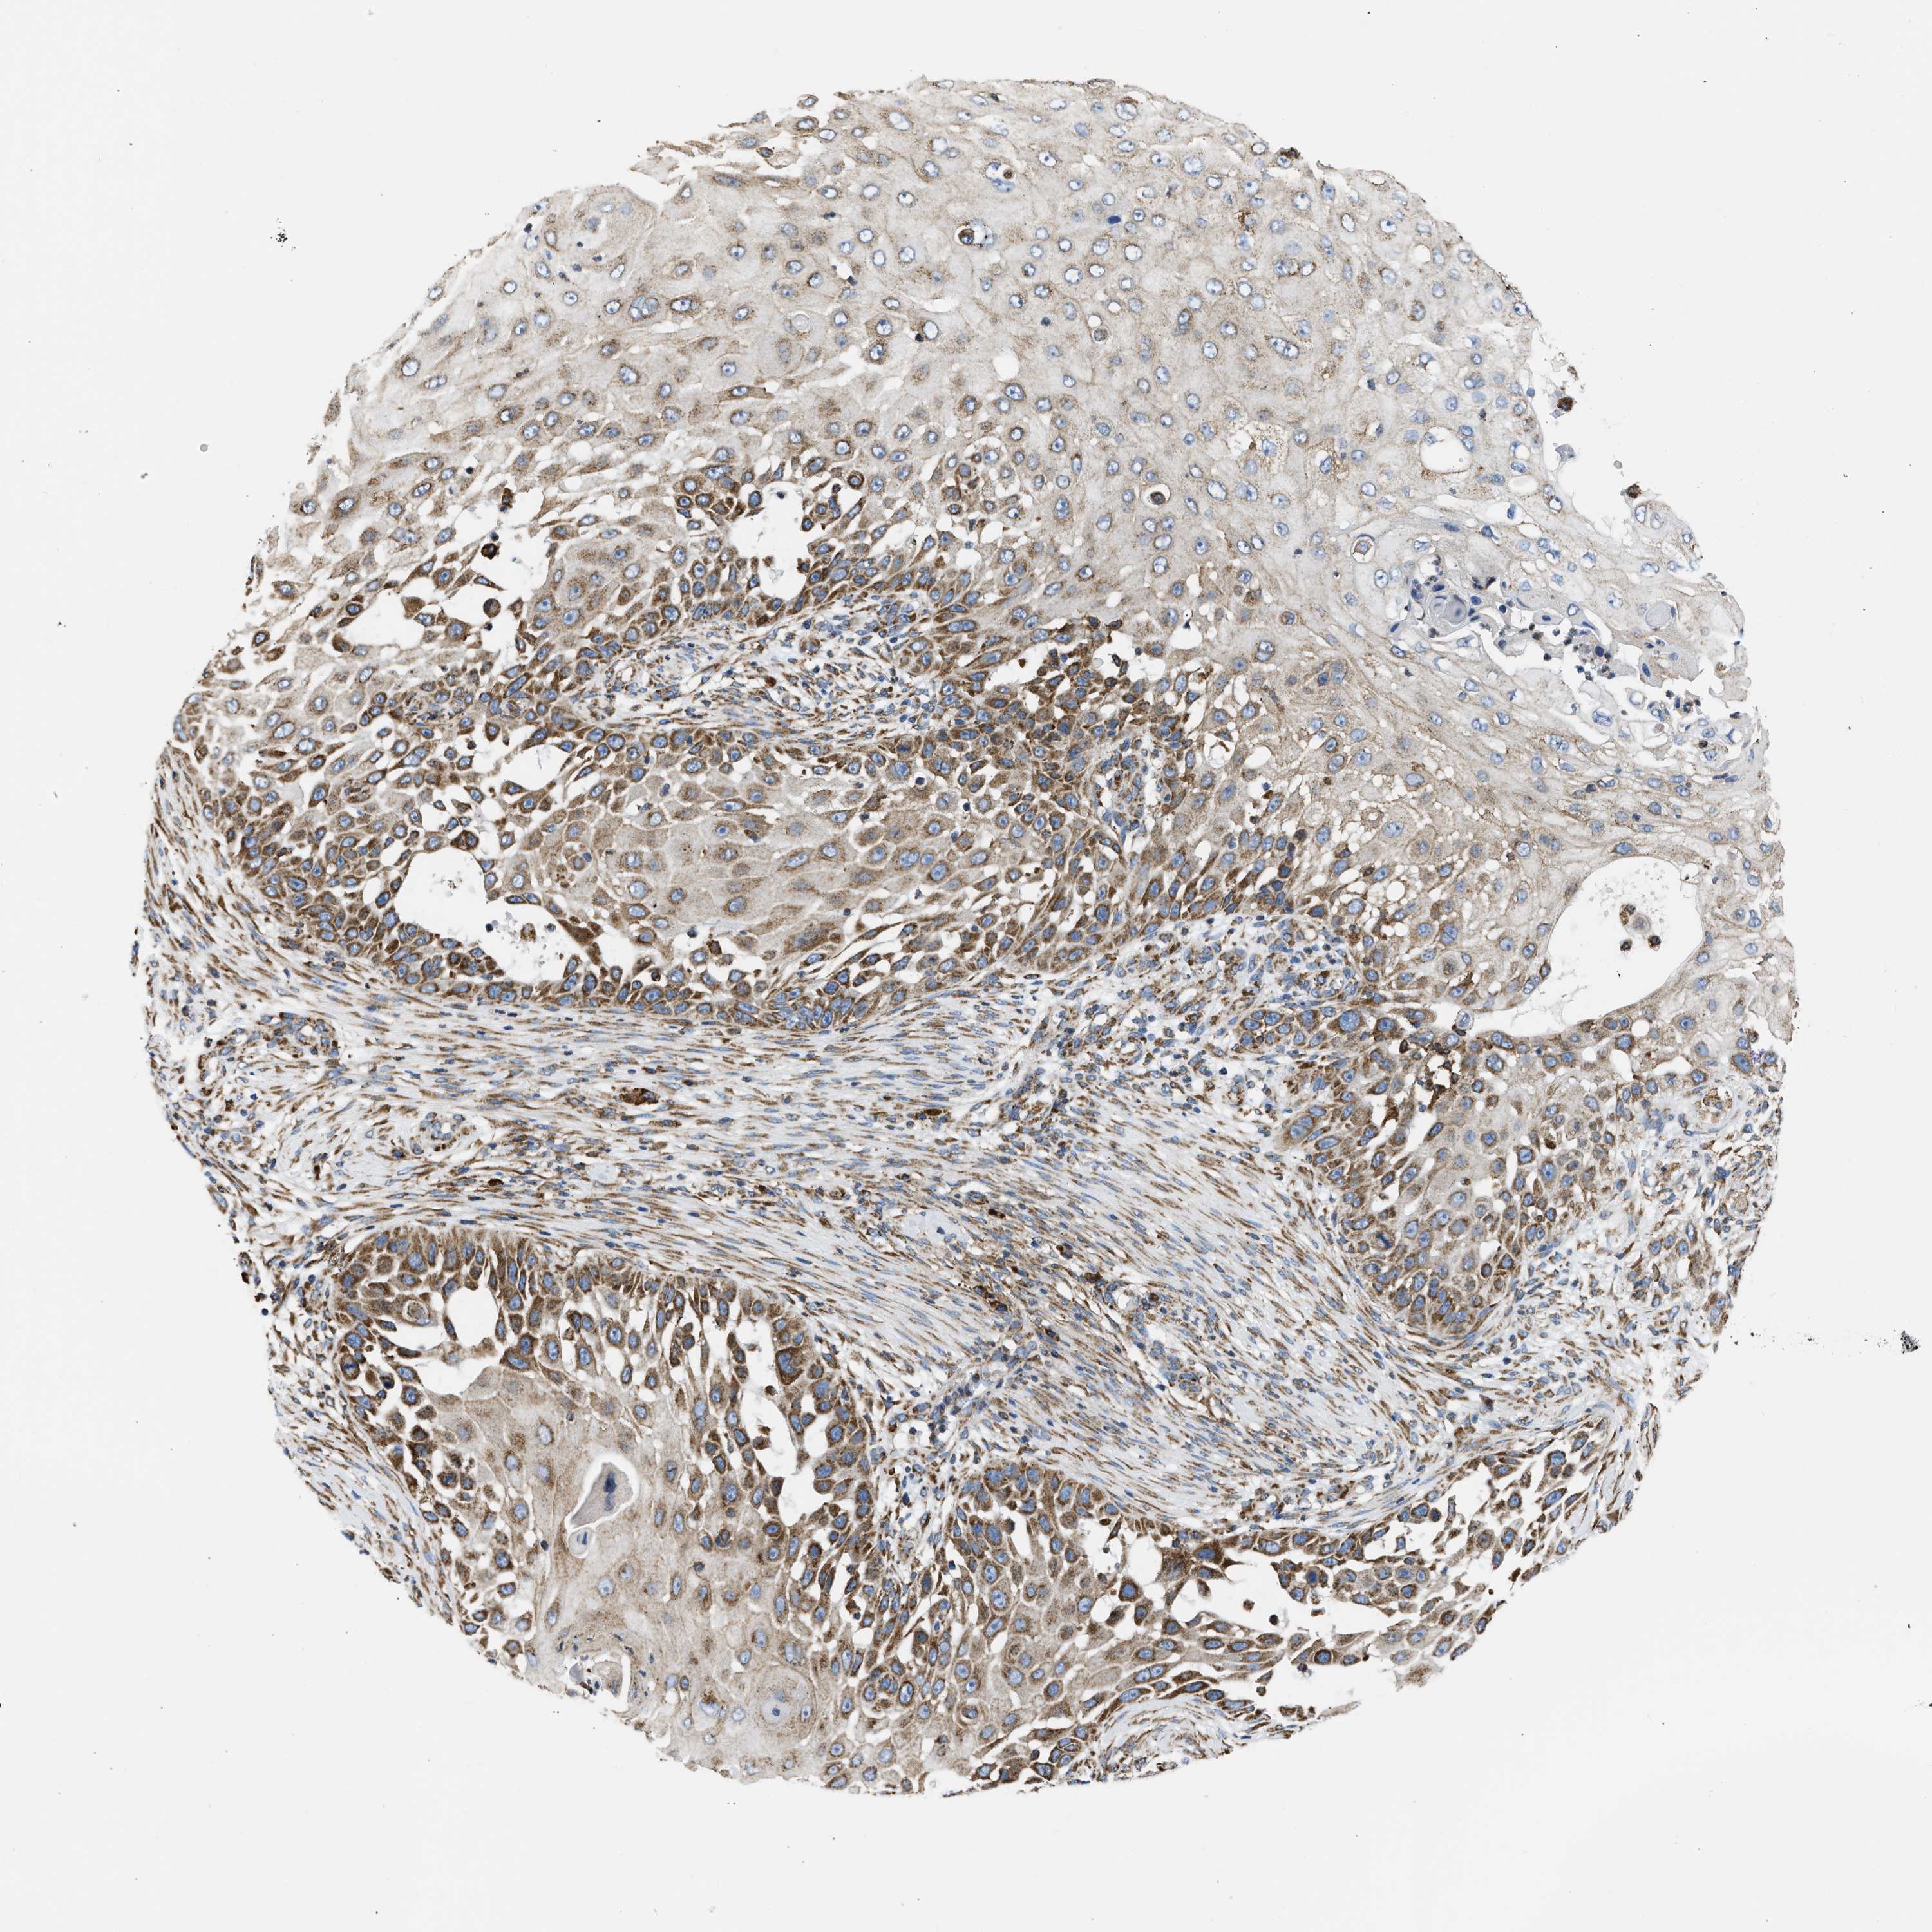

SKIN CANCER - Protein expressioni

A mouse-over function shows sample information and annotation data. Click on an image to view it in a full screen mode. Samples can be filtered based on level of antibody staining by selecting one or several of the following categories: high, medium, low and not detected. The assay and annotation is described here.

Antibody stainingi

Antibody staining in the annotated cell types in the current human tissue is reported as not detected, low, medium, or high, based on conventional immunohistochemistry profiling in selected tissues. This score is based on the combination of the staining intensity and fraction of stained cells.

Each image is clickable and will lead to virtual microscopy that enables deeper exploration of all samples and also displays staining intensity scores, fraction scores and subcellular localization as well as patient and tissue information for each sample.

Antibody CAB004222

Staining

High

Medium

Low

Not detected

Intensity

Strong

Moderate

Weak

Negative

Quantity

>75%

75%-25%

<25%

None

Location

Nuclear

Cytoplasmic/membranous

Cytoplasmic/membranous,nuclear

Squamous cell carcinoma, NOS